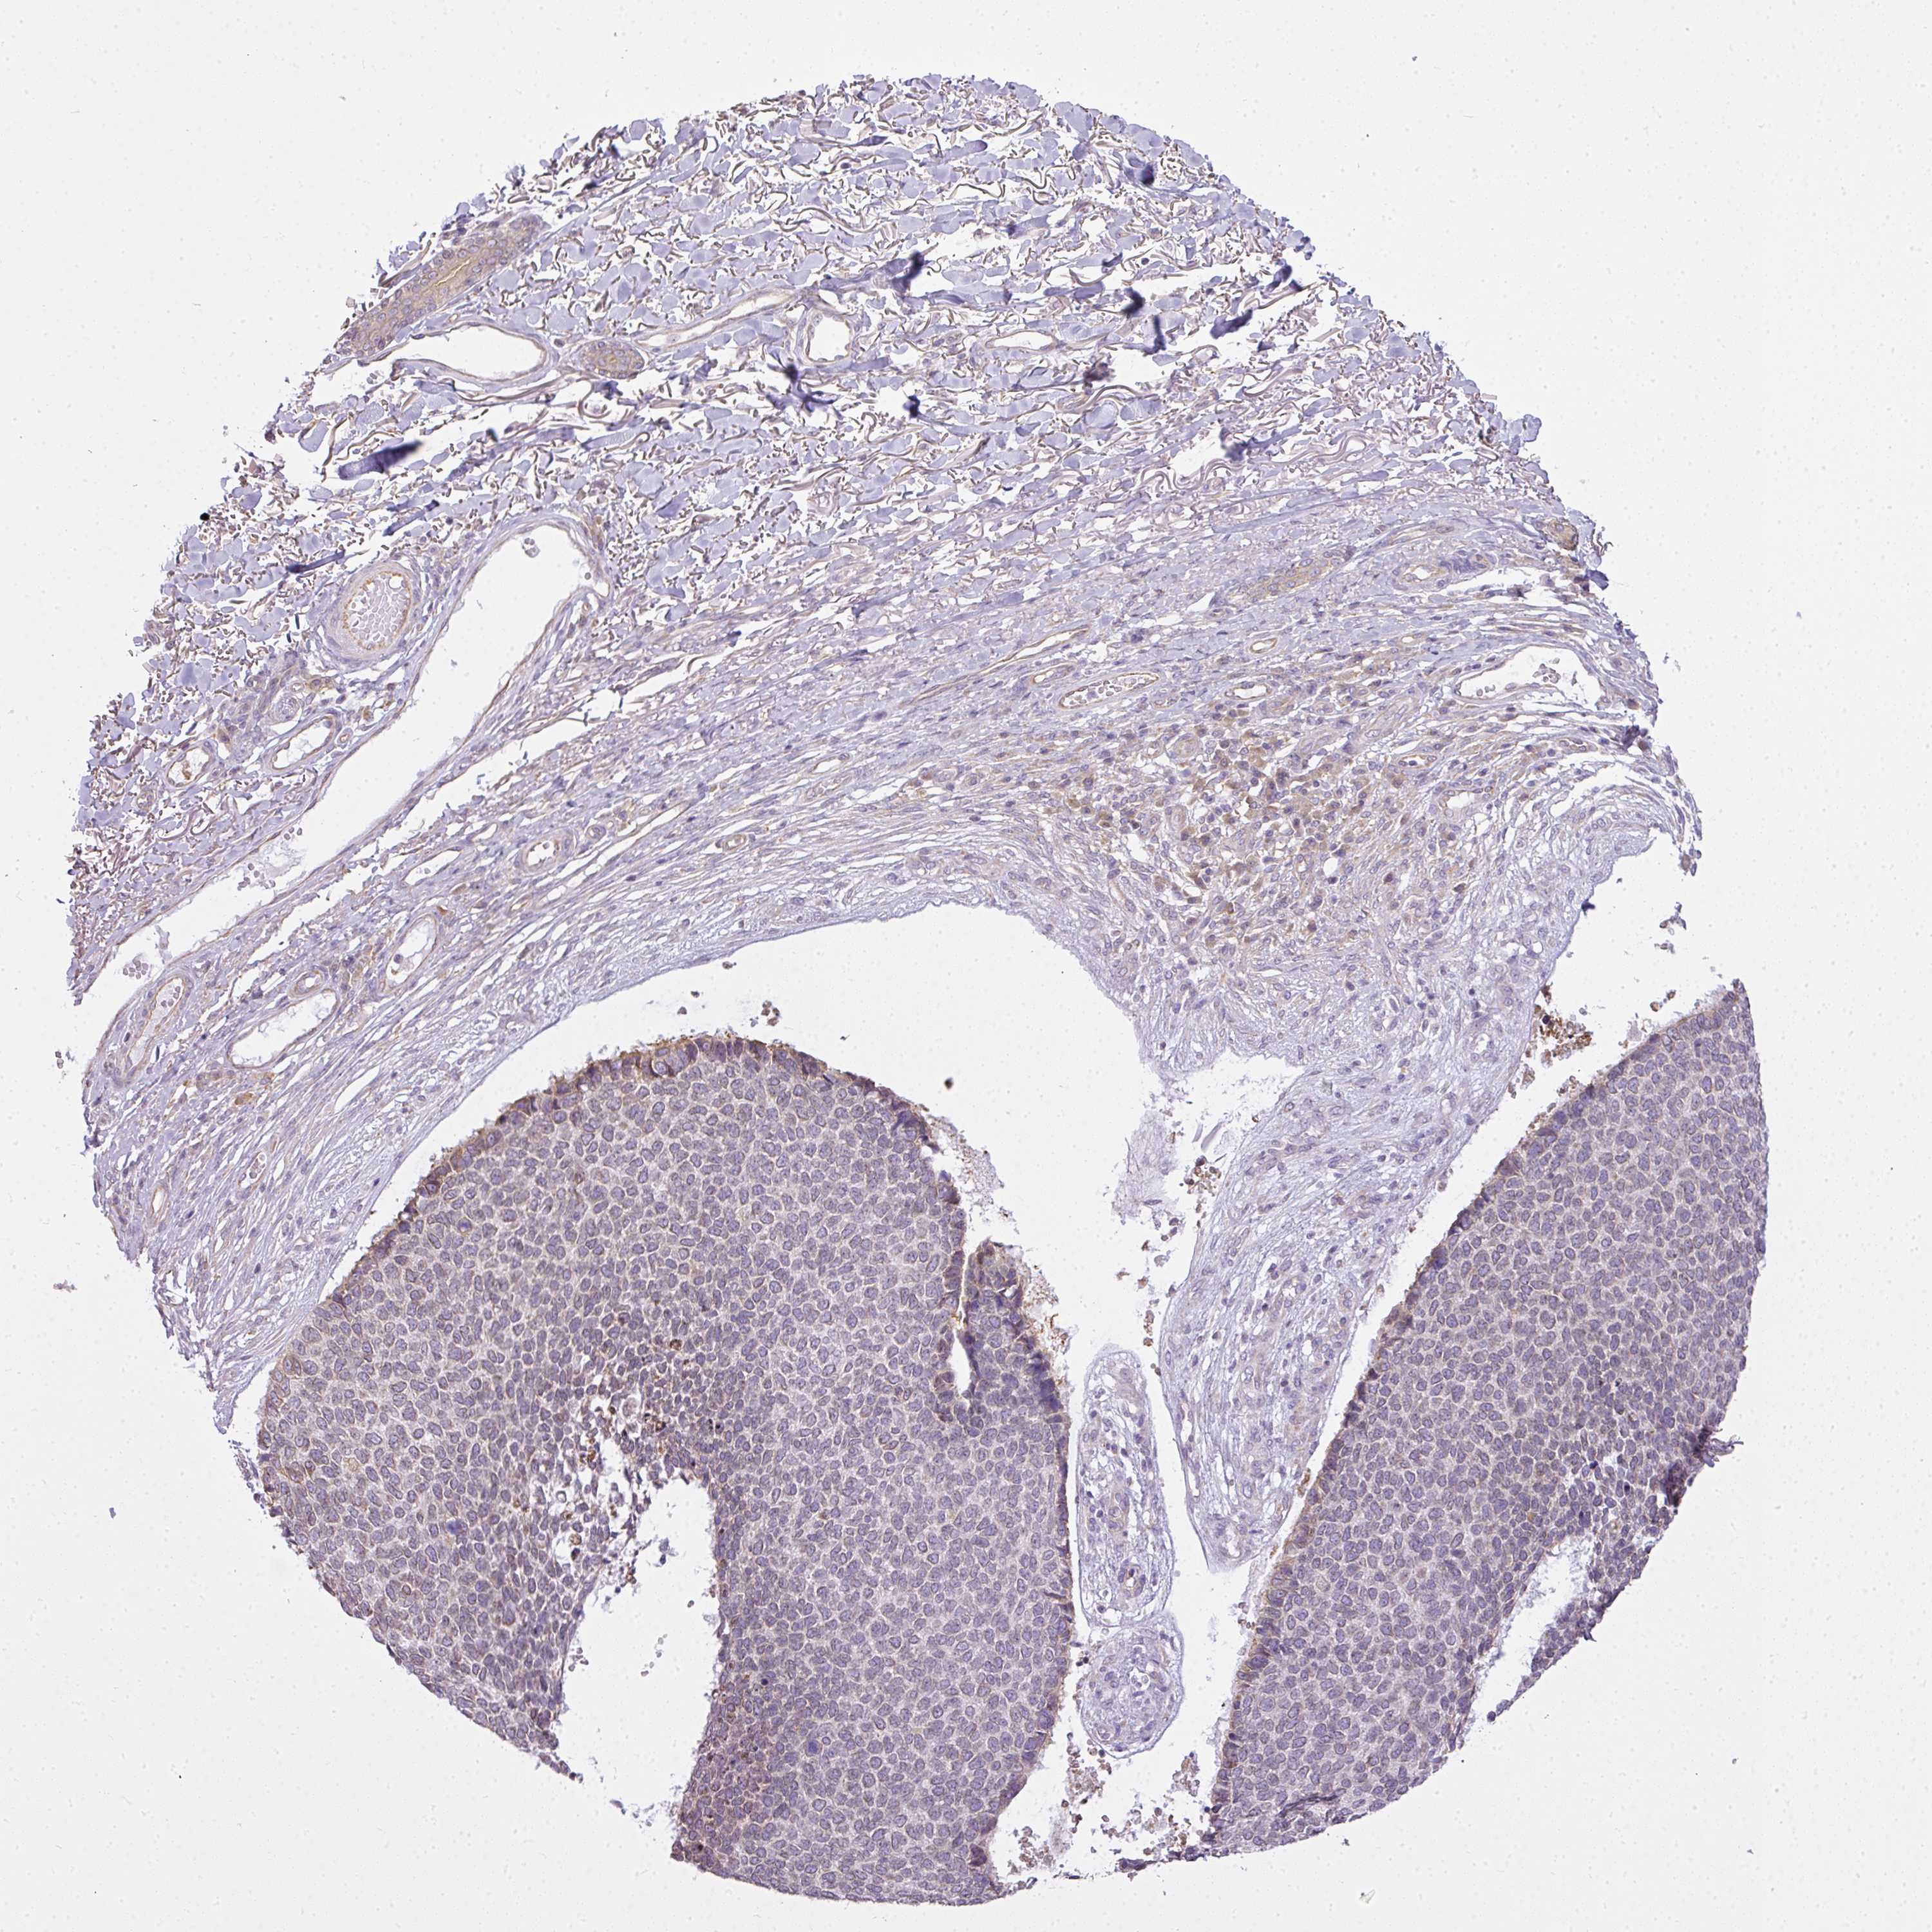

SKIN CANCER - Protein expressioni

A mouse-over function shows sample information and annotation data. Click on an image to view it in a full screen mode. Samples can be filtered based on level of antibody staining by selecting one or several of the following categories: high, medium, low and not detected. The assay and annotation is described here.

Antibody stainingi

Antibody staining in the annotated cell types in the current human tissue is reported as not detected, low, medium, or high, based on conventional immunohistochemistry profiling in selected tissues. This score is based on the combination of the staining intensity and fraction of stained cells.

Each image is clickable and will lead to virtual microscopy that enables deeper exploration of all samples and also displays staining intensity scores, fraction scores and subcellular localization as well as patient and tissue information for each sample.

Antibody HPA046772

Antibody HPA049489

Staining

Intensity

Strong

Moderate

Weak

Negative

Quantity

>75%

75%-25%

<25%

None

Location

Nuclear

Cytoplasmic/membranous

Cytoplasmic/membranous,nuclear

Basal cell carcinoma

Squamous cell carcinoma, NOS

Squamous cell carcinoma, metastatic, NOS